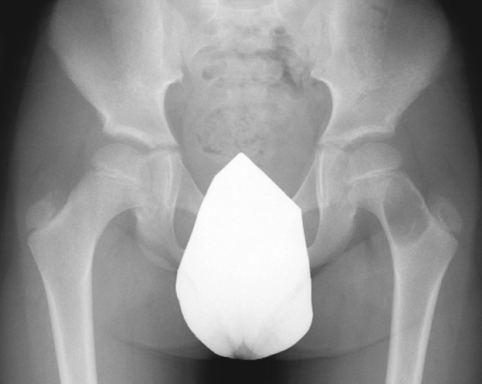

unicameral bone cyst

Gregory F. Hayden, MD; Nathan T. Cohen, MD, BS; Mark J. Romness, MD

<p>A 9-year-old boy presents with a 10-day history of left leg pain and limp. The pain waxes and wanes, and it increases with ambulation. The limp worsens with activity. The boy plays soccer but has...